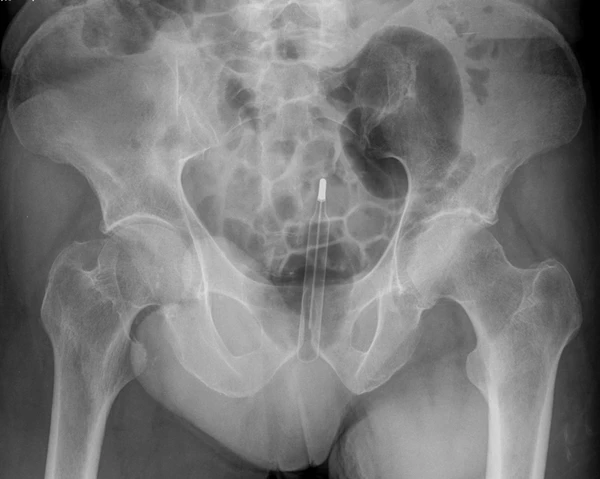

Обычно делают несколько рентгеновских снимков, чтобы точно определить место нахождения инородного тела. Инородные тела из малоконтрастного материала (например, пластика) могут потребовать ультразвукового исследования или компьютерной томографии[23]. Магнитно-резонансная томография противопоказана, особенно если неизвестен материал инородного тела. Инородные тела прямой кишки могут проникать глубоко в толстую кишку, при определённых обстоятельствах вплоть до правого изгиба ободочной кишки[9].